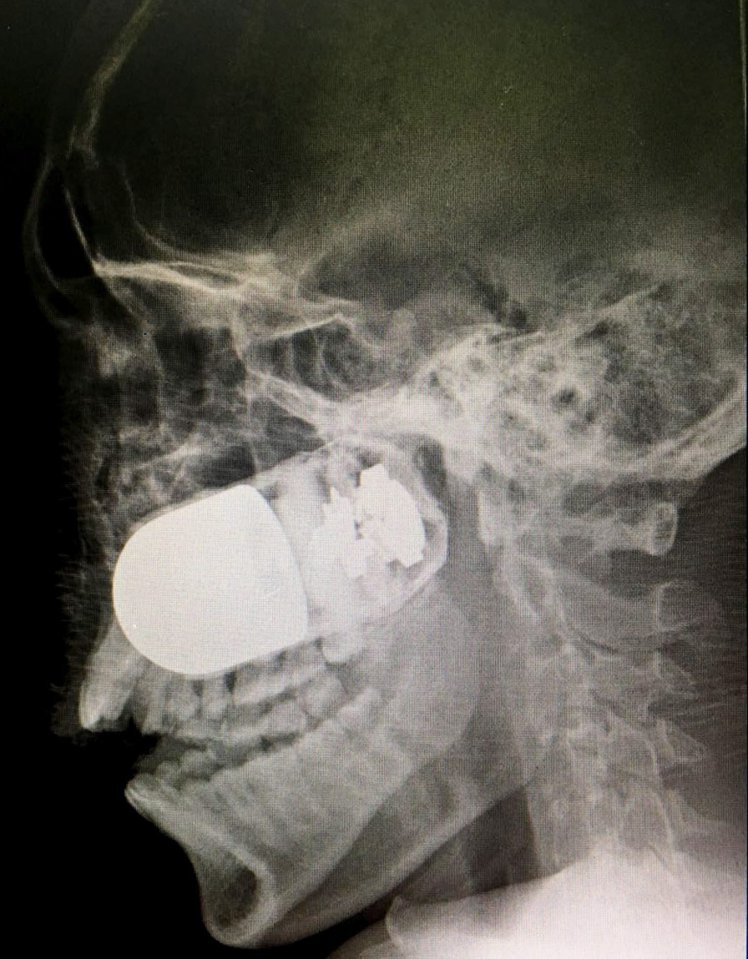

Yes, that is a live grenade lodged in the skull of a soldier.

Colombian Military doctors had to carry out a risky operation to remove the grenade at a hospital in capital Bogota.

If that wasn’t strange enough the procedure was apparently carried out in the car park of the facility where a temporary operating theatre was set up, to keep the rest of the hospital out of harm’s way

This was just in case the explosive detonated.

The chief of surgery, William Sanchez, said: ‘It was a decisive moment, logically one of stress and uncertainty, but there was no other option than to push on to save the life of the patient, even praying and asking God not to let a bigger tragedy happen.’

The surgeon described how the team carried out the operation with the utmost care, not only to save the life of the patient, but to preserve their own, seeing as the explosive could have gone off at any time.